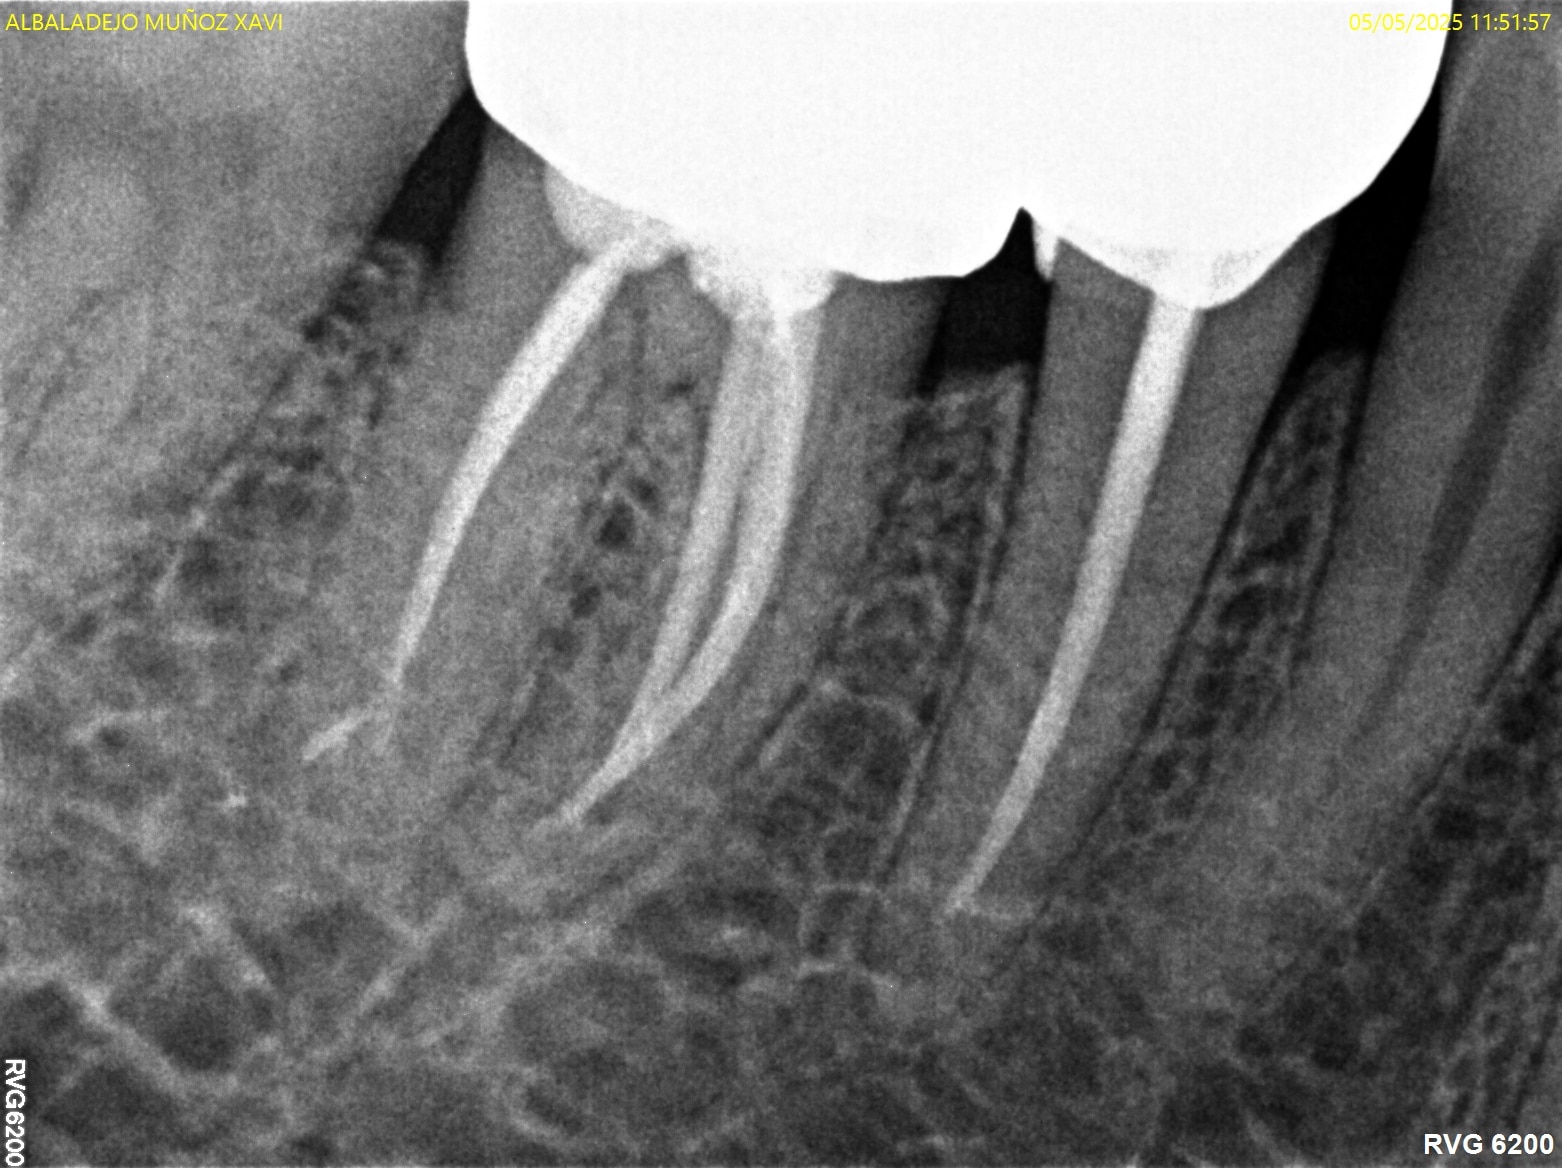

Caso 2

Paciente con presencia de caries extensas, se realiza tratamiento de conductos en 45-46 y posterior restauración con coronas cerámicas.